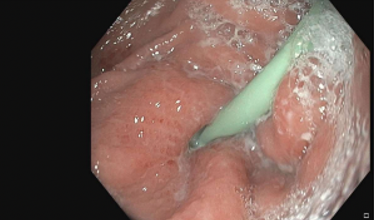

- Confirmed via endoscopy

- Endoscopic view of buried bumper

Image from personal library of Katelyn Cookson

Figure 1. Gastric Body, buried internal bumper